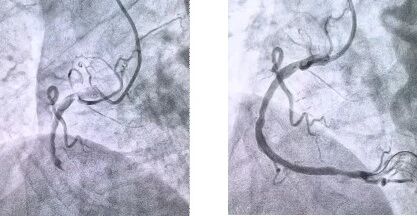

患者抵达医院后,简化挂号、缴费等中间环节,迅速沟通病情,需要紧急介入治疗,获得家属同意,立即送至导管室。造影显示其右冠状动脉中段完全闭塞,医生迅速实施血栓抽吸,球囊扩张和药物洗脱支架植入术。36 分钟后,闭塞血管恢复正常血流,吴大爷的血压、心率逐渐平稳,胸痛症状明显缓解。术后三天,他便转入普通病房进行康复训练,重拾健康生活。